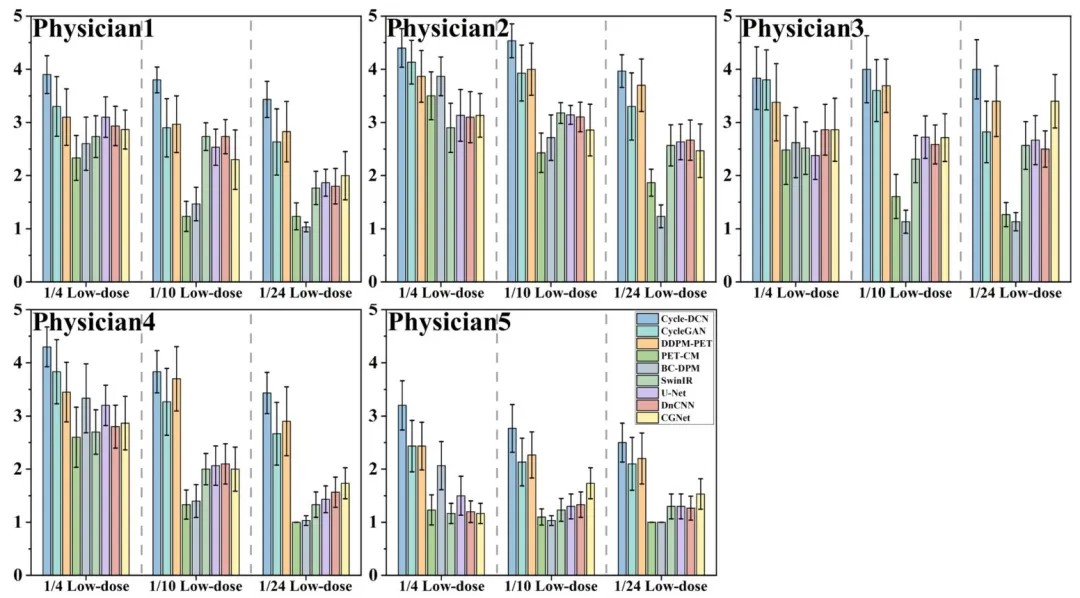

Fig. 8. The scoring results from the five physicians for different models on the randomly selected 30 cases in the test dataset.

图8 五位医师对测试数据集中随机选取的30个病例,针对不同模型的评分结果。